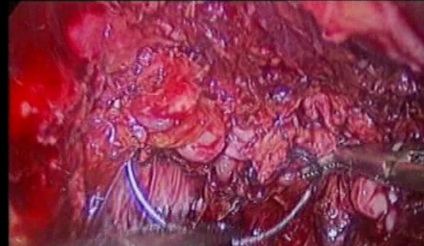

Endometrial cancer is cancer of the lining of the uterus. The treatment of early stage endometrial cancer is a simple hysterectomy and, in select cases, pelvic lymphadenectomy (specialized organs which drain tissue fluid). Laparoscopic surgery is the route of choice for treatment of endometrial cancer.